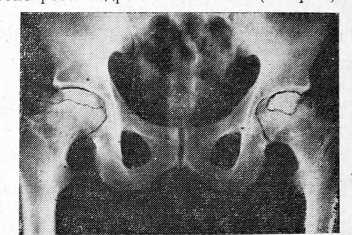

И., 45 лет, в 1966 г. после простуды внезапно почувствовал боли в правом бедре с иррадиацией по всей нижней конечности «до пятки» и в поясницу. Через 4 года подобные боли появились и слева. Был установлен диагноз «хронический пояснично-крестцовый радикулит», по поводу которого больного ежегодно госпитализировали в неврологическое отделение ЦРБ; неоднократно И. ездил на грязевые курорты. Только через 8 лет, когда обнаружилось прогрессирующее ухудшение функции тазобедренных суставов, при очередной рентгенографии был диагностирован запущенный двусторонний коксартроз на почве идиопатического остеонекроза бедренных головок (см. рис. 1).

Рис. 1. Рентгенограмма больного И. Двусторонний остеонекроз головок бедренных костей.